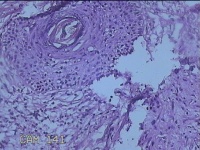

左面部肿物

性别

女

年龄

35岁

临床诊断

皮脂腺增生 囊肿?

一般病史

左面部起疹30年。

标本名称

大体所见

灰白粉红色肿物1x0.8x0.3cm一个,表面糜烂,切开肿物呈实性,切面灰白粉红色,质软。